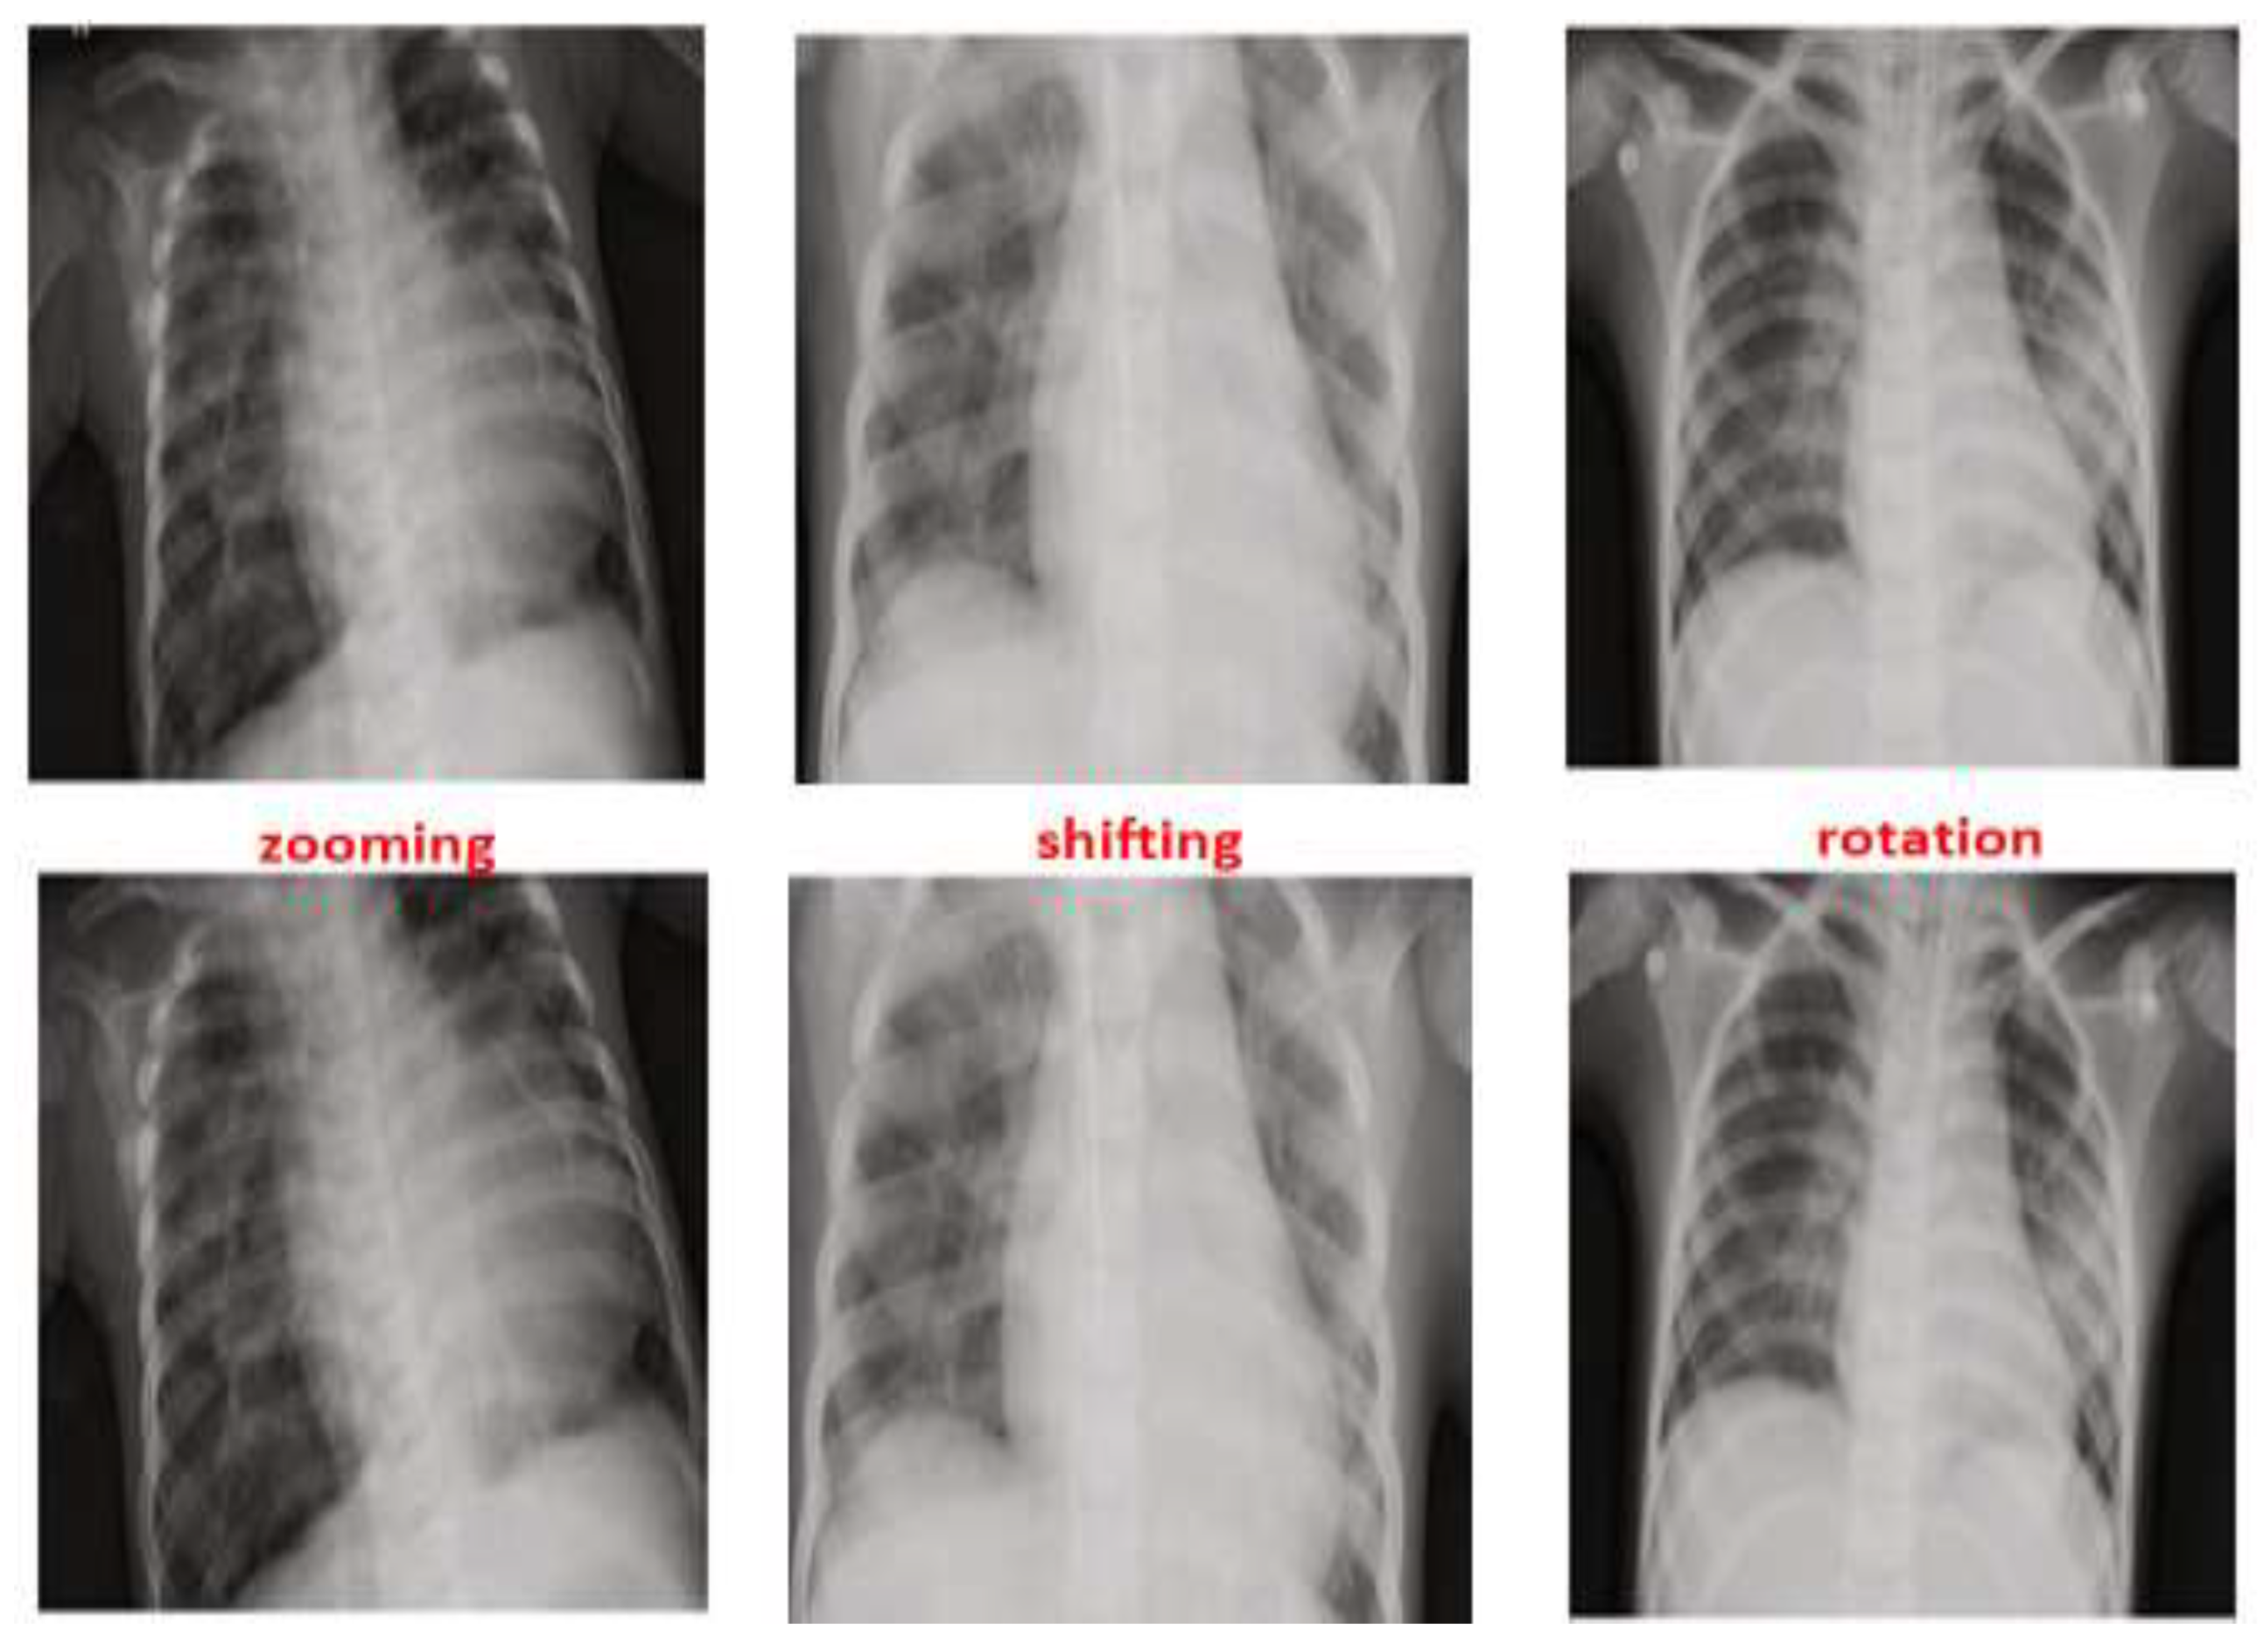

As seen in Figure 5, zooming, flipping, shifting and rotation operations were used in the augmentation process to balance the distribution of the scans between Normal and Pneumonia cases. After applying the augmentation process to the Normal class, the number of normal cases increased from 1583 cases to 7915 cases. By contrast, the augmentation process for the Pneumonia class was performed on 75% of the 4273 using only one operation from the augmentation operations that was selected randomly. This results in an increase of the Pneumonia cases reaching a new total of 7478. This led to the reduction in the IR of Normal and Pneumonia cases from 46% to 2.8%, which is considered a huge improvement.

Figure 5. Three cases and their corresponding augmentation methods: zooming, shifting and rotation.